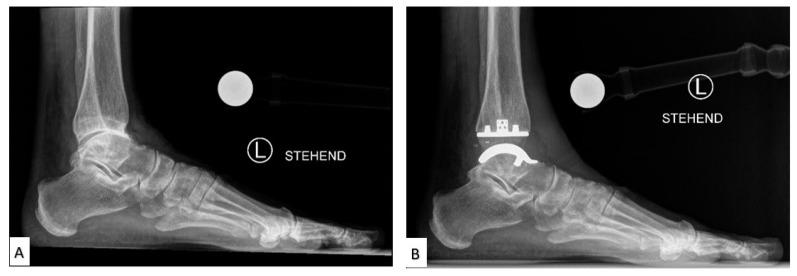

The foot and ankle serve vital roles in weight bearing, balance, and flexibility but are susceptible to many diverse ailments, making treatment difficult. More commonly, Total Ankle Arthroplasty (TAA) and Total Talus Replacement (TTR) are used for patients with ankle degeneration and avascular necrosis of the talus, respectively. Ankle prosthesis and orthosis are also indicated for use with lower limb extremity amputations or locomotor disability, leading to the development of powered exoskeletons. However, patient outcomes remain suboptimal, commonly due to the misfitting of implants to the patient-specific anatomy. Additive manufacturing (AM) is being used to create customized, patient-specific implants and porous implant cages that provide structural support while allowing for increased bony ingrowth and to develop customized, lightweight exoskeletons with multifunctional actuators. AM implants and devices have shown success in preserving stability and mobility of the joint and achieving fast recovery, as well as significant improvements in gait rehabilitation, gait assistance, and strength for patients. This review of the literature highlights various devices and technologies currently used for foot and ankle prosthesis and orthosis with deep insight into improvements from historical technologies, manufacturing methods, and future developments in the biomedical space.

足踝在负重、平衡和灵活性方面起着至关重要的作用,但易患多种不同疾病,这使得治疗变得困难。更常见的是,全踝关节置换术(TAA)和距骨全置换术(TTR)分别用于患有踝关节退变和距骨缺血性坏死的患者。踝关节假体和矫形器也适用于下肢截肢或运动功能障碍的患者,从而推动了动力外骨骼的发展。然而,患者的治疗效果仍然不尽人意,这通常是由于植入物与患者特定解剖结构不匹配所致。增材制造(AM)正被用于制造定制的、针对患者的植入物和多孔植入物笼,这些植入物和笼子在提供结构支撑的同时,还能促进骨长入增加,并开发具有多功能致动器的定制轻质外骨骼。增材制造的植入物和设备在保持关节稳定性和活动能力以及实现快速康复方面已取得成功,同时在患者的步态康复、步态辅助和力量方面也有显著改善。这篇文献综述重点介绍了目前用于足踝假体和矫形器的各种设备和技术,并深入洞察了从历史技术、制造方法到生物医学领域未来发展的改进情况。